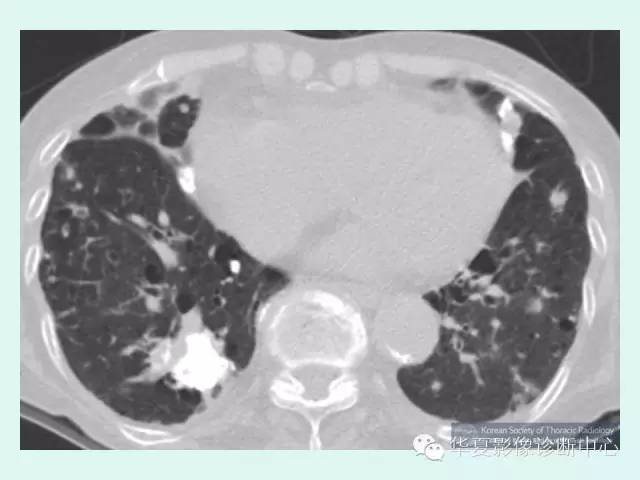

肺淀粉样变性1例CT影像表现

【病例】肺淀粉样变性1例CT影像表现